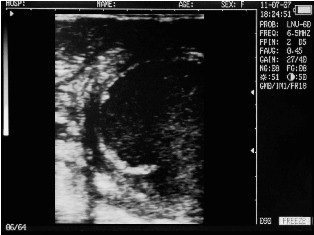

Ultrasound images of cows reproductive system, generated by a scanner Sonovet with rectal linear transducer.

Filled bladder cow